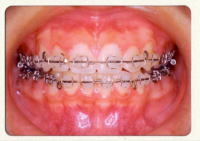

使用する装置

目立ちにくいセラミックブラケットを使用します。

咬み合せの状態によっては、下の歯にメタルブラケットを使用します。